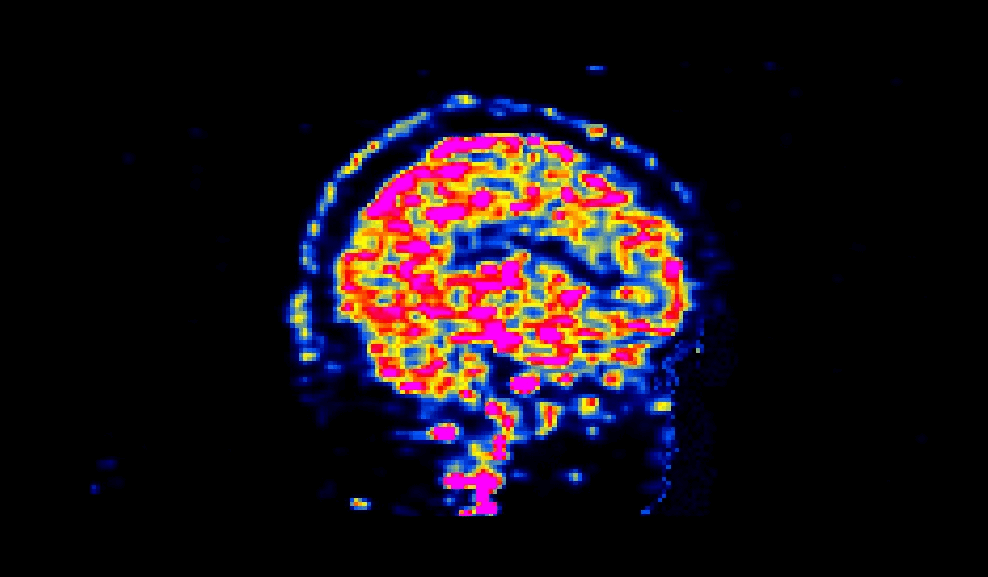

When viewed, a succesfully defaced PET image will have varying intensities in the face region, as shown below:

_images/sagittal.gif